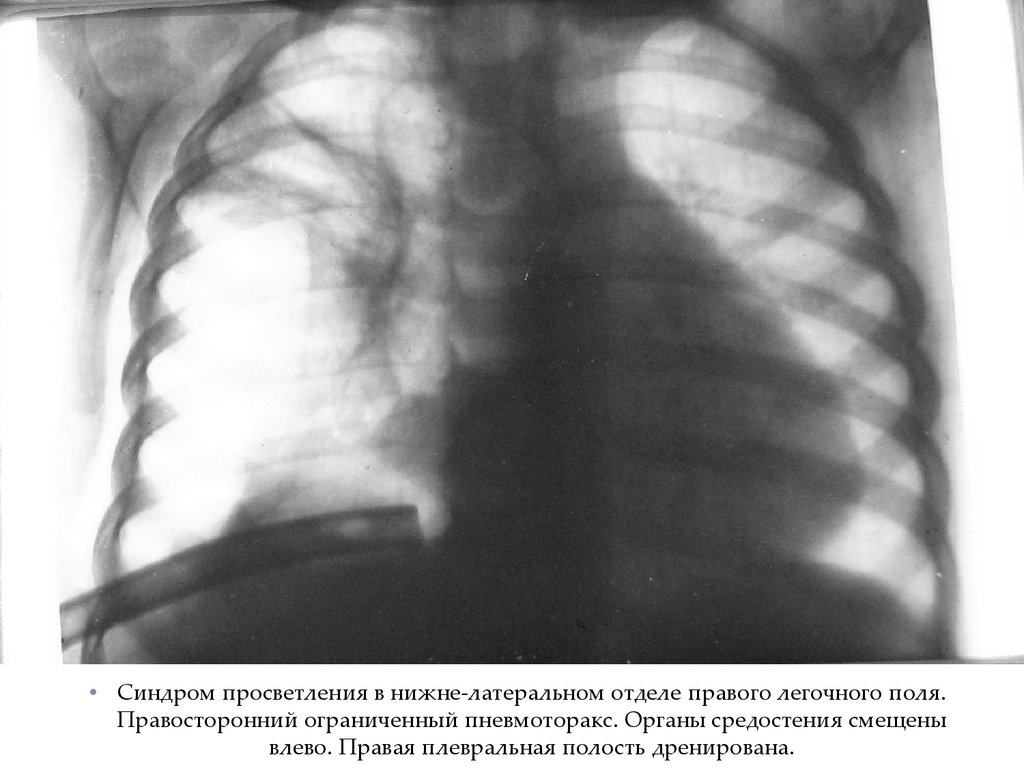

• Синдром просветления в нижне-латеральном отделе правого легочного поля.

Правосторонний ограниченный пневмоторакс. Органы средостения смещены

влево. Правая плевральная полость дренирована.